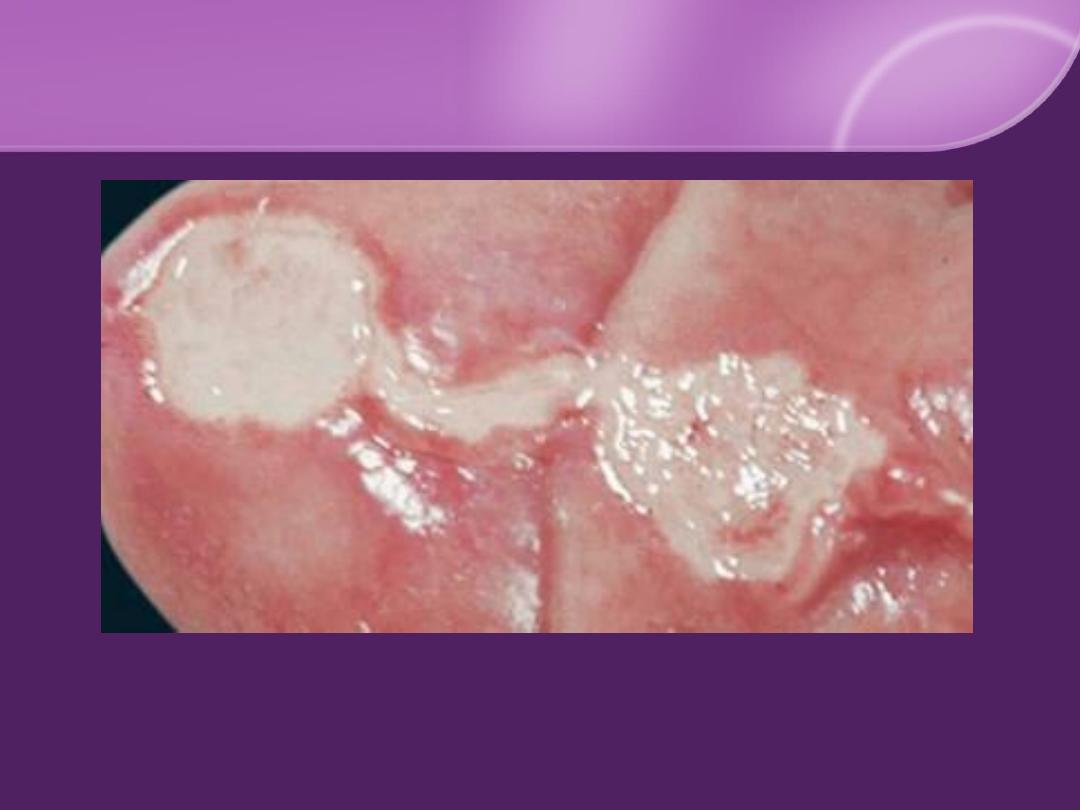

MM Lesions:

palate, nasal mucosa, tongue, tonsils, and pharynx

Oral leukoplakia

50%